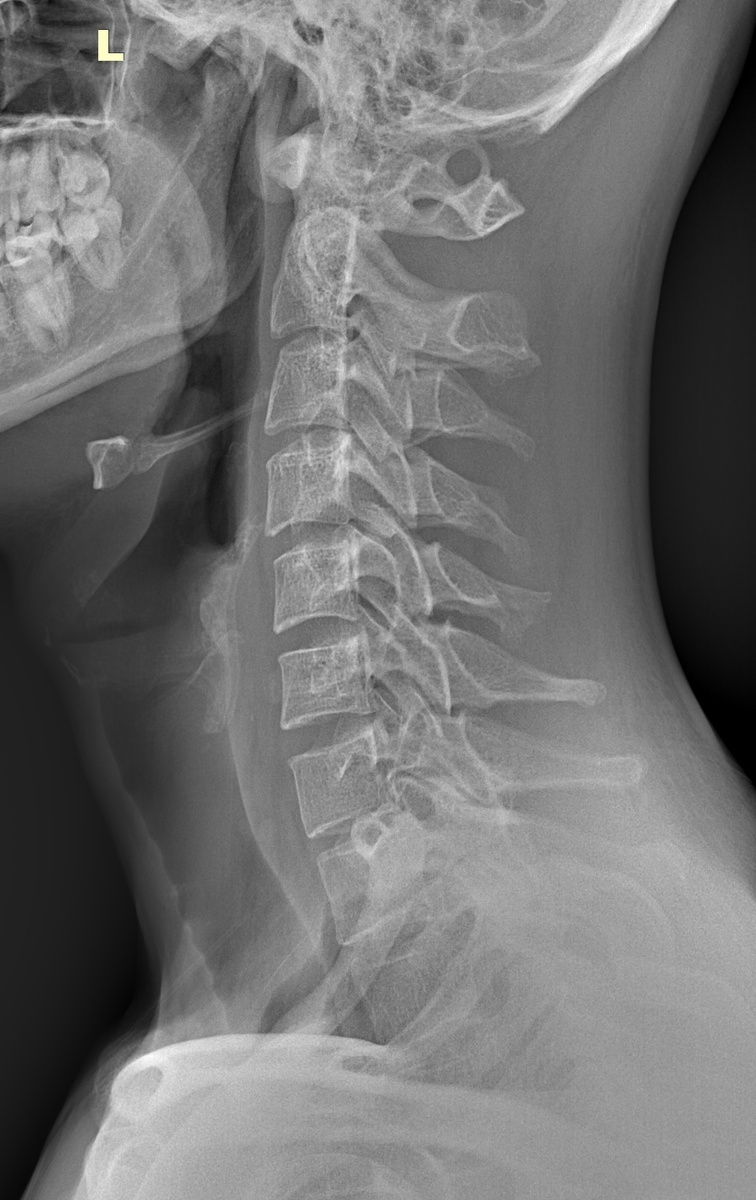

Аномалия Киммерли. Рентген - боковой снимок с согнутой шеей

Аномалия Киммерли. Рентген снимок в боковой проекции.